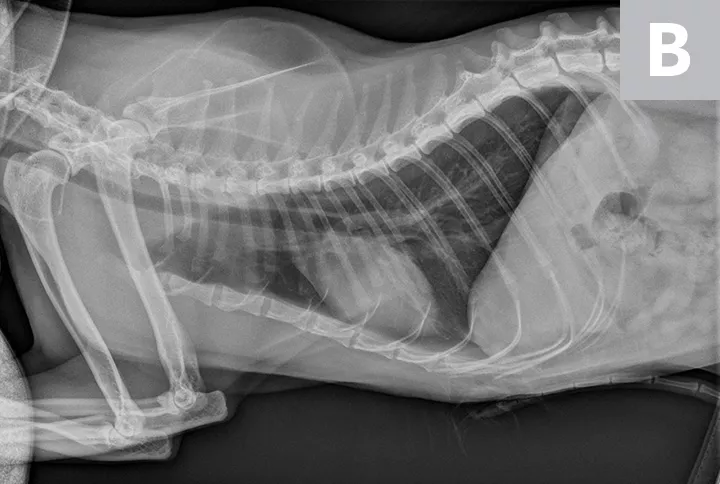

FIGURE 1A

Lateral radiographs of a 2-year-old cat (A) and a 9-year-old cat with increased sternal contact of the cardiac silhouette (B).